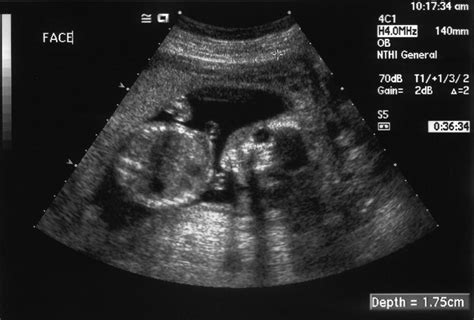

Kritickým faktorom je aj stará jazva po cisárskom reze. Ak žena otehotnie príliš skoro po sekcii, nápor nového tehotenstva by nemusela jazva vydržať a hrozí jej pretrhnutie. „Klinické skúsenosti ukazujú, že interval medzi cisárskym rezom a následnou tehotnosťou je dôležitý. Riziko pretrhnutia maternice je trikrát vyššie, ak je interval kratší ako osemnásť mesiacov. Ak odstup dodržíte, môžete skúsiť rodiť prirodzene,“ hovorí MUDr.Vladimír Cupaník. Na sonografické meranie jazvy sa pritom netreba spoliehať, pretože neexistujú relevantné údaje o ultrazvukovom meraní hrúbky steny maternice. Aby sa predišlo pretrhnutiu, často sa tieto tehotenstvá ukončujú predčasne.